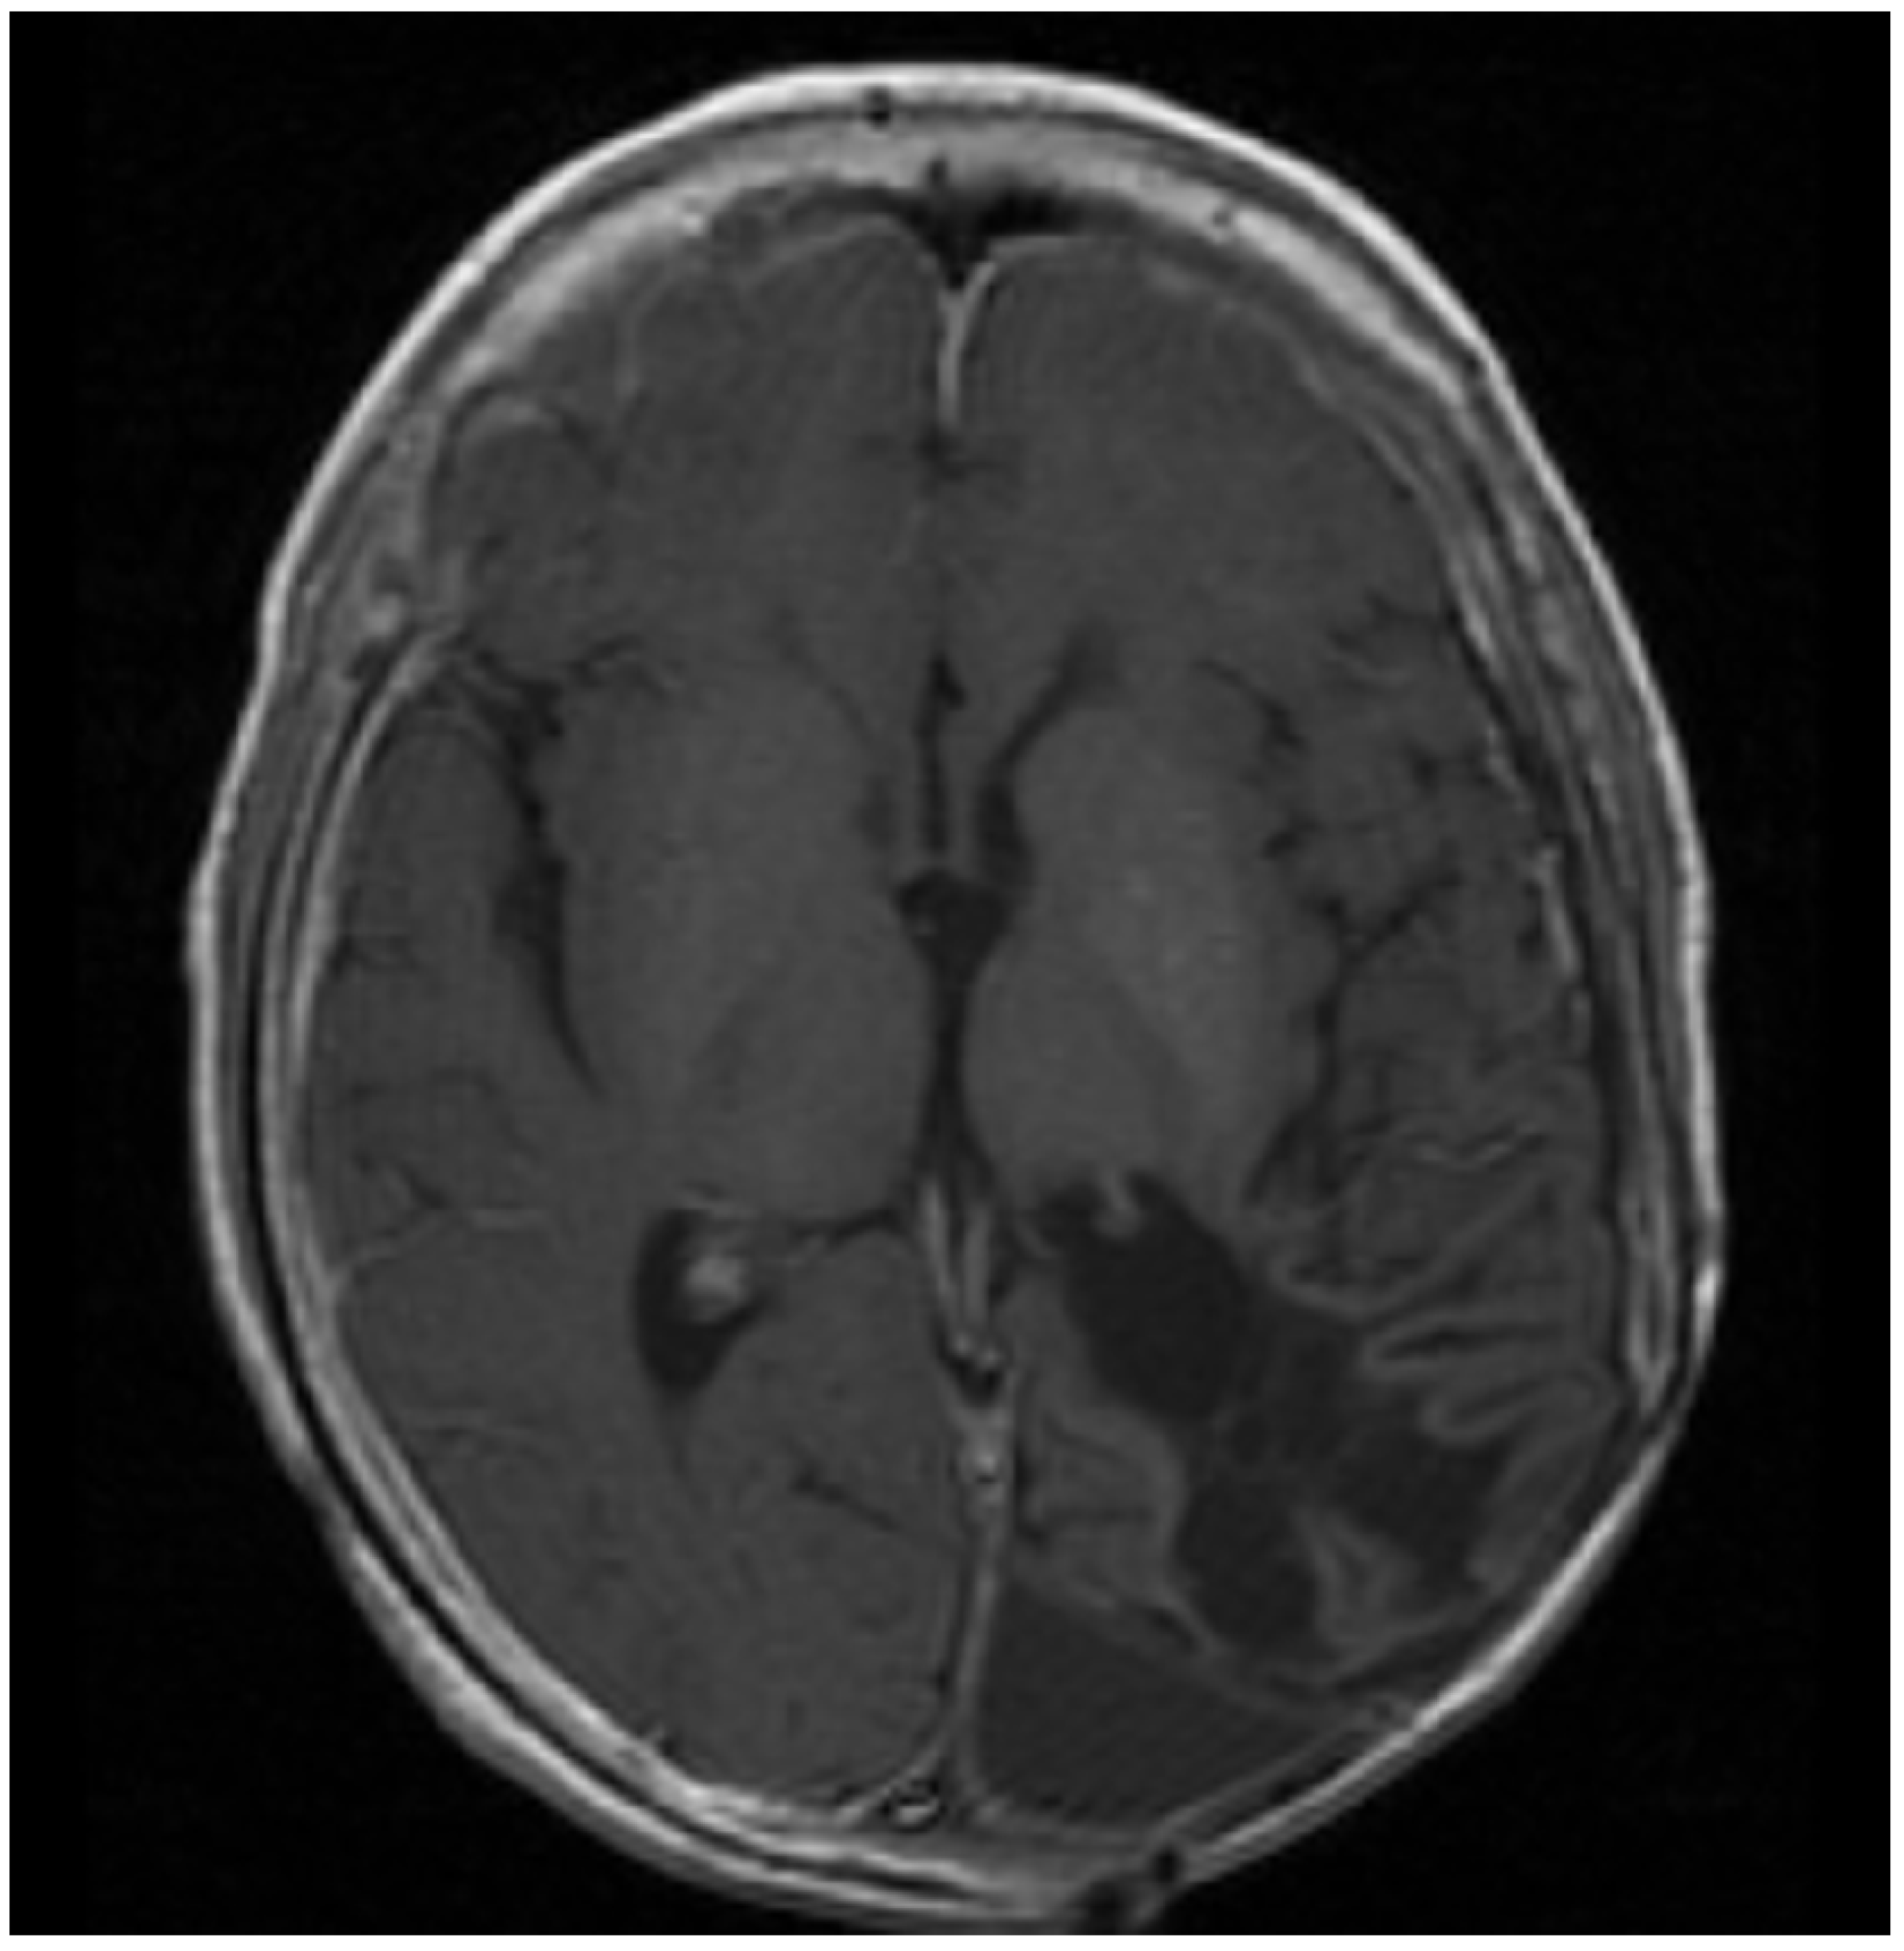

Figure 2.

Patient 2: MRI shows confluent encephalomalacia gliosis in the left temporal and occipital lobes. There was no evidence of mass or pathologic enhancement 8 years from diagnosis and 4 years off therapy.

Patient 2 was diagnosed with anaplastic ependymoma when he presented with right hemianopsia, severe vision loss, and a 12 cm × 8 cm × 8 cm left temporo-occipital tumor at 6 years of life. He had two consecutive surgeries to remove the tumor, but a 1 cm unresectable lesion was left behind. He then received 5940 cGy field radiation to the tumor bed. Three months after radiation, he developed seizures, transient right arm paralysis, and recurrent disease to the left cerebral hemisphere, for which he received vincristine, carboplatin, and cyclophosphamide following the guidelines of ACNS0121 [35]. Three months later, he developed progressive disease with a large infiltrative enhancing mass (~5 cm) in the left temporal, occipital, and parietal lobes with involvement of the left thalamus, internal capsule, left external capsule, and insula, as well as leptomeningeal metastasis to the thoracic spine. He had no access to Phase I or II studies and was unable to travel for lack of insurance and migratory status, for which treatment was changed to palliation chemotherapy with oral VP16 (50 mg/m2/day for 21 days) alternating with oral CTX (50 mg/m2/day for 21 days) and continuous celecoxib (120 mg/m2 PO bid) and VA. Celecoxib was subsequently changed to sulindac (8 mg/kg/day) due to drug access issues. He had an excellent response to palliation with resolution of all enhancing lesions and no evidence of residual disease after 2 years of therapy. (Figure 2). About this time VA was added to his seizure disorder management and continued until his last visit. He received 18 additional months of metronomic chemotherapy after complete response. He had no evidence of recurrent disease when he was lost to follow up 8 years from initial diagnosis and 4 years off metronomic chemotherapy. This patient showed complete response to the metronomic regimen.